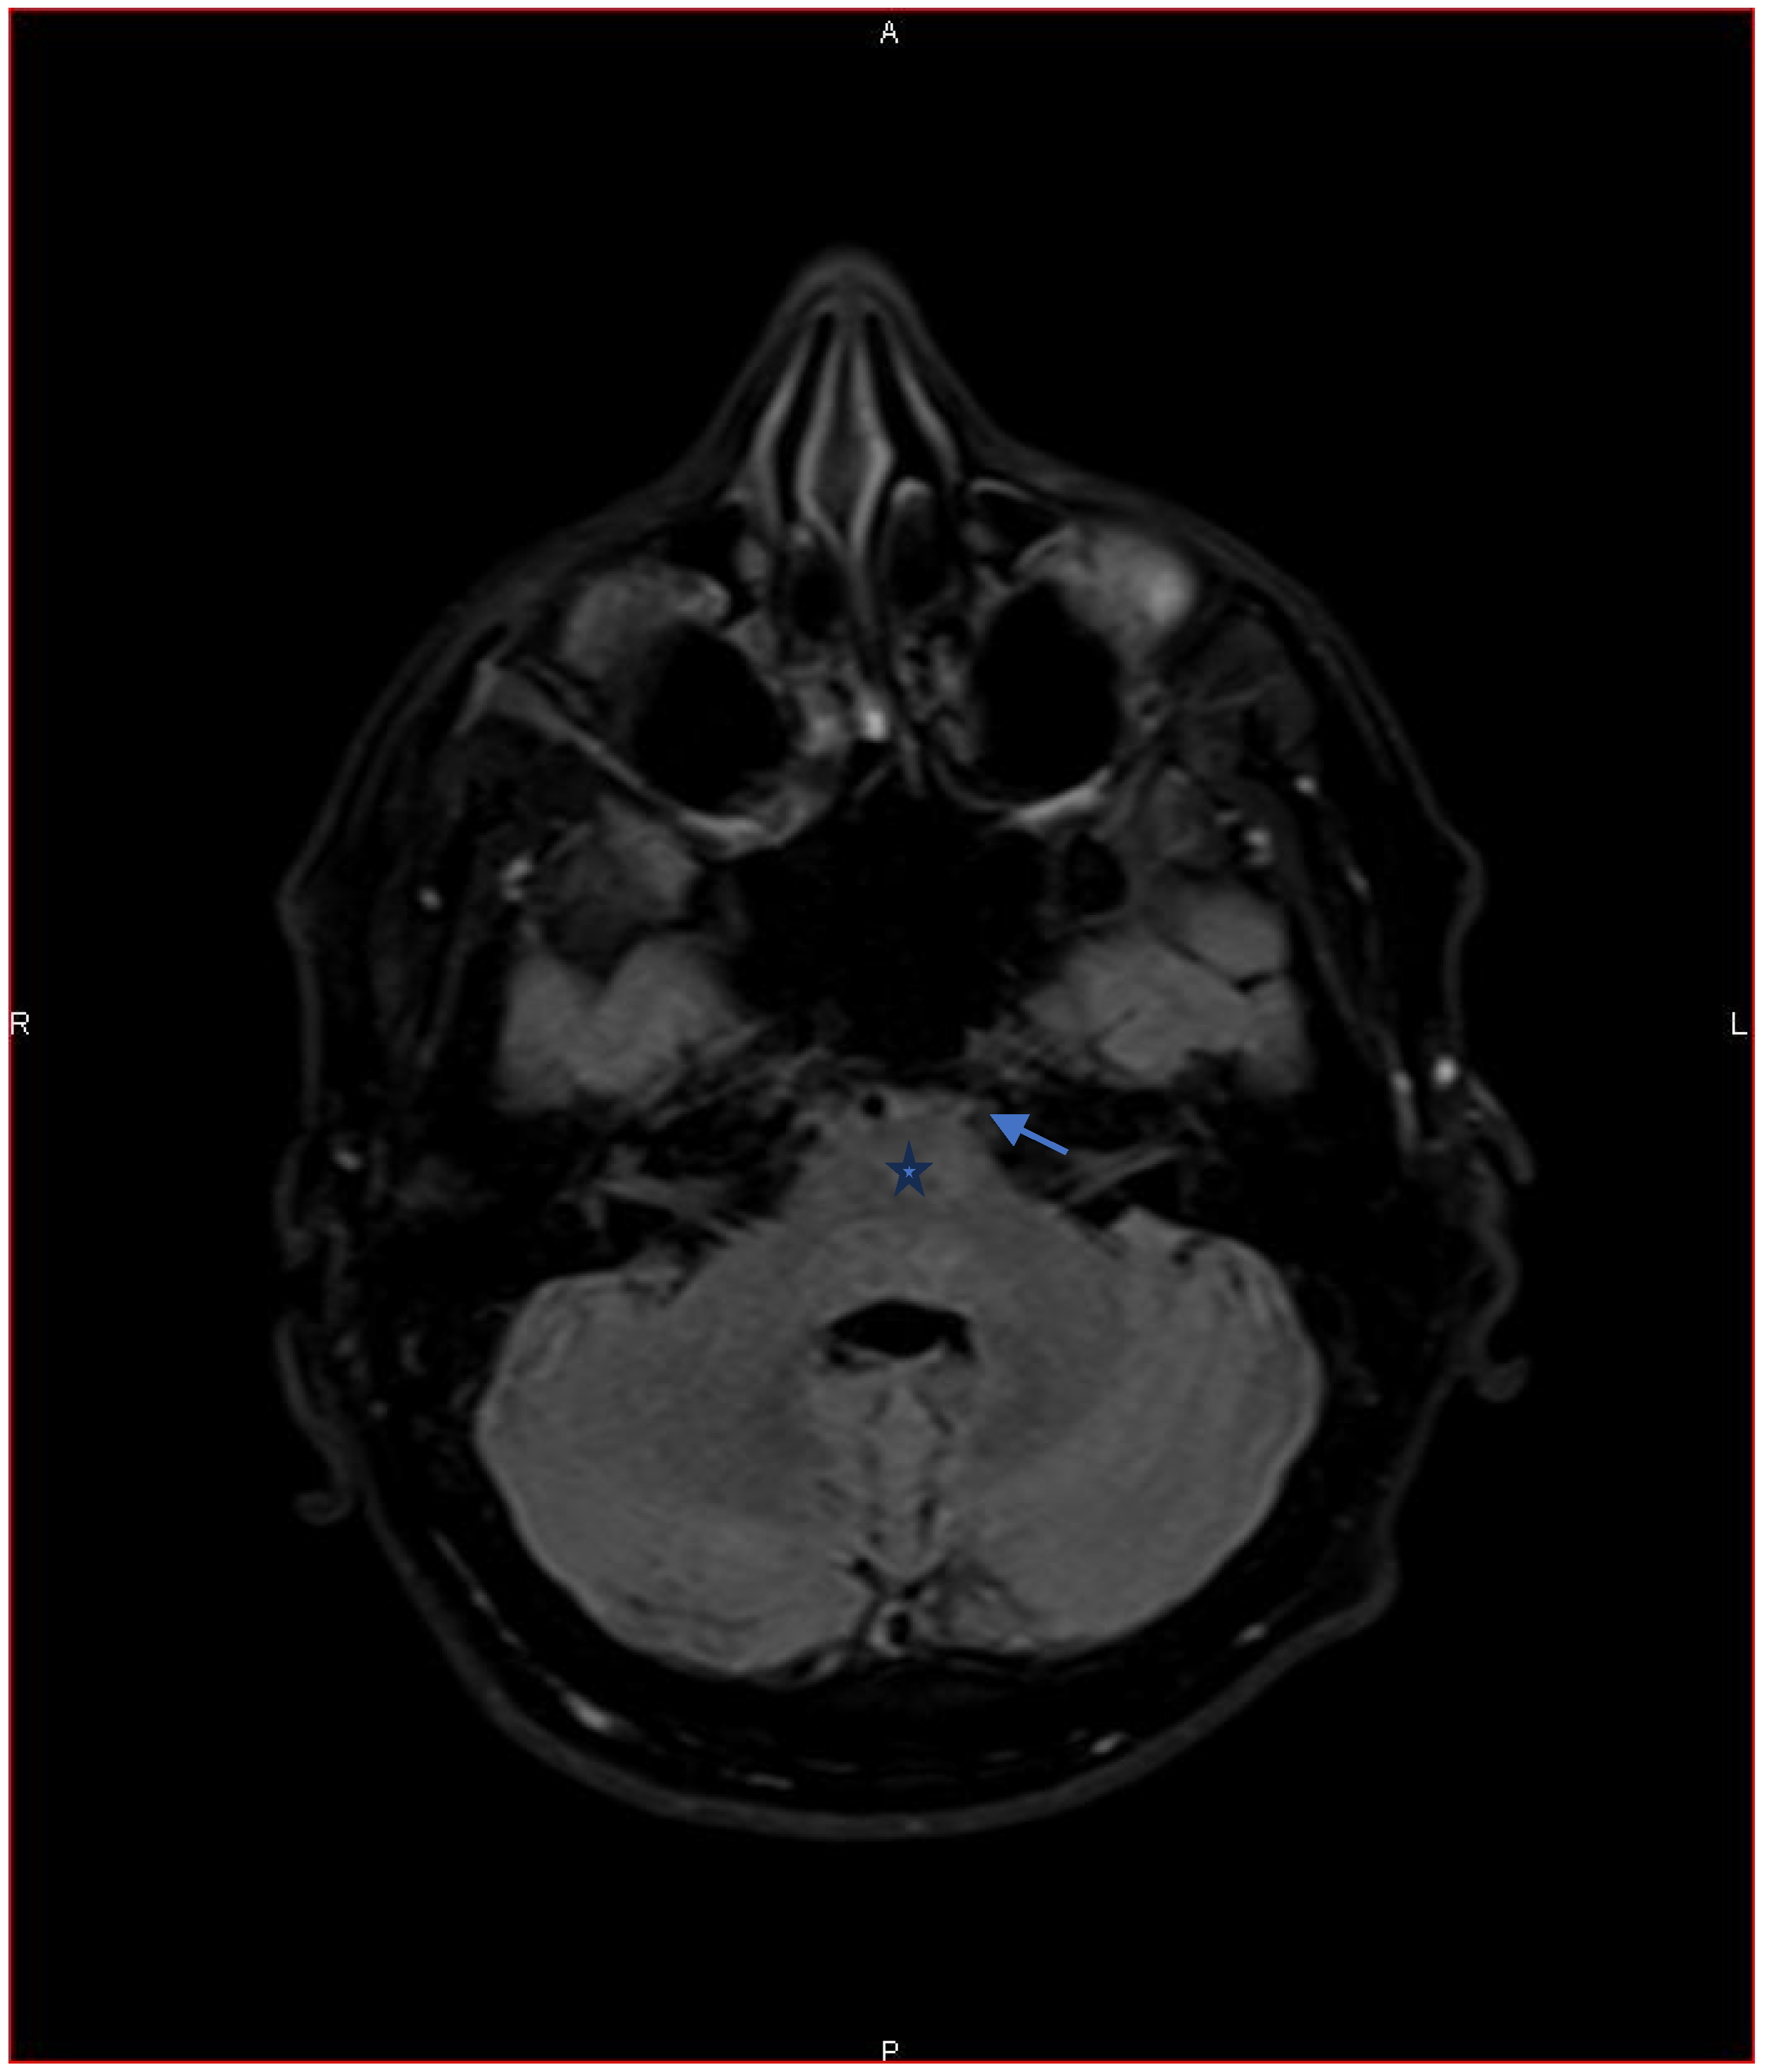

Peripapillary retinal nerve fiber layer optical coherence tomography (OCT) (Figure 2), ganglion cell complex (inner nuclear layer + ganglion cells layer) OCT (Figure 3), and automated visual field examinations (Figure 4) were normal. A gadolinium-enhanced magnetic resonance imaging (MRI) was performed and was reported normal (Figure 5). General laboratory tests, including complete blood count, C-reactive protein (CRP), erythrocyte sedimentation rate (ESR), angiotensin-converting enzyme, syphilis, Human Immunodeficiency Virus (HIV) serologies, and tuberculosis testing were normal. Borrelia Serologic testing for Borrelia showed negative IgM antibodies and positive IgG antibodies (111.8 UA/mL) on enzyme-linked immunosorbent assay (ELISA). These findings were confirmed by Western blot analysis.

A review of the brain MRI was requested, focusing on the region between the pons and the petro-clinoid ligament. Imaging revealed signs of neuritis of the left sixth cranial nerve. The seventh cranial nerve could not be clearly visualized (Figure 6).

Figure 5. Axial FLAIR T2 without gadolinium MRI focusing on the region of the pons and reported normal. The arrow shows the emergence of the sixth left cranial nerve. The star shows the pons.